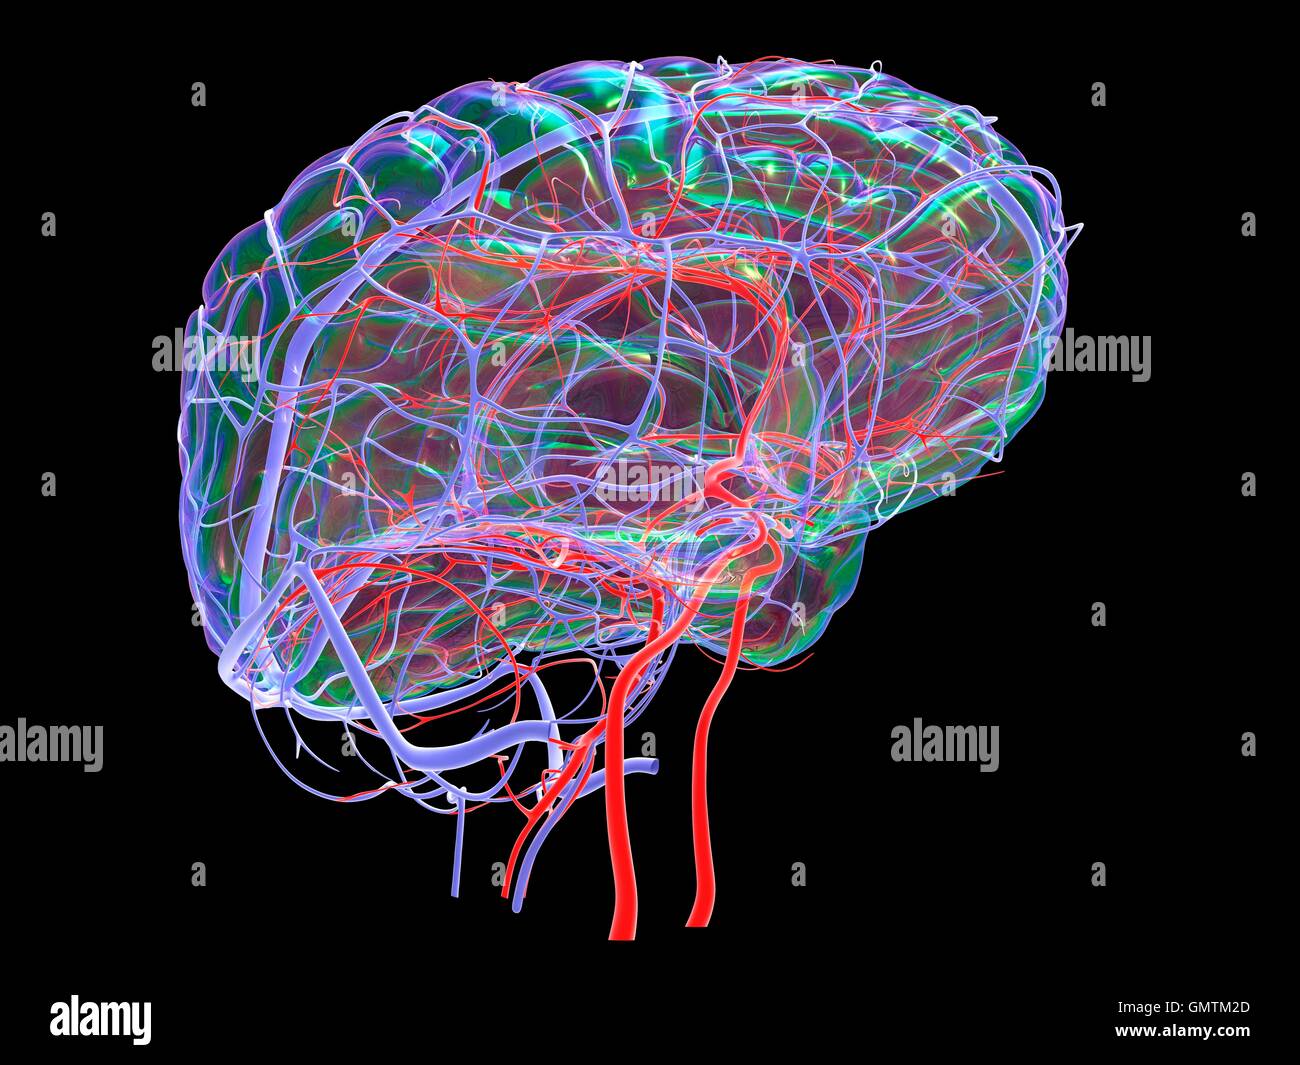

RFGMTM2D–Gehirn-System und Blut Gefäßversorgung. Grafik zeigt das Gehirn mit Arterien (rot) und Venen (blau).

RFR3P9KW–Illustration der Blutversorgung des Gehirns. Das Gehirn hat wenig Kapazität, Nährstoffe zu speichern, aber es braucht eine hohe Versorgung mit Sauerstoff und Glukose.

RMJE9NWM–Dieses anatomische Bild zeigt die Arterien unter dem Gehirn, einem wichtigen Teil des menschlichen Kreislaufsystems. Die Arterien sind dafür verantwortlich, das Gehirn mit Blut zu versorgen und seine Funktion zu gewährleisten. Die Nahansicht hilft beim Verständnis ihrer Struktur und Rolle für die Gesundheit und Funktion des Gehirns.

RFGMTM21–Gehirn-System und Blut Gefäßversorgung. Grafik zeigt das Gehirn mit den richtigen Großhirn entfernt und Arterien (rot) und Venen (blau).

RFR3P9KC–Illustration der Blutversorgung des Gehirns. Das Gehirn hat wenig Kapazität, Nährstoffe zu speichern, und benötigt eine hohe Versorgung mit Sauerstoff und Glukose.